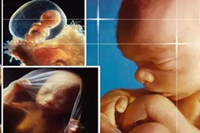

胎兒五個(gè)月時(shí)性器官已經(jīng)發(fā)育完善,你有沒有好奇懷孕五個(gè)月男胎兒長(zhǎng)什么樣呢?如果你對(duì)此感興趣,不如一起來看看懷孕五個(gè)月男胎兒圖長(zhǎng)啥樣...

懷孕六個(gè)月男胎兒圖什么樣?相信這是所有孕媽都感興趣的話題吧。懷孕進(jìn)入六個(gè)月后,此時(shí)孕媽會(huì)越來越感覺得到胎兒的存在,大多數(shù)的孕媽這個(gè)時(shí)候已經(jīng)擺脫了妊娠的各種不良癥狀...